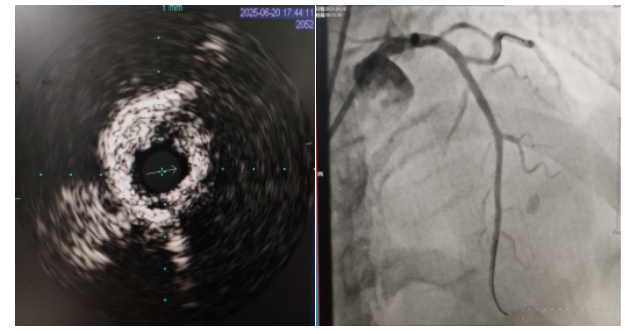

術(shù)中,趙慶禧主任醫(yī)師、雷剛副主任醫(yī)師運用IVUS血管內(nèi)超聲技術(shù)評估,發(fā)現(xiàn)患者前降支、對角支0.1.1型真性分叉病變,前降支近中段嚴(yán)重鈣化、成角并99%狹窄,對角支近段嚴(yán)重鈣化并99%狹窄,傳統(tǒng)冠狀動脈旋磨術(shù)容易引起冠狀動脈穿孔,決定采用沖擊波球囊技術(shù)即血管內(nèi)沖擊波鈣化碎裂術(shù)對患者嚴(yán)重鈣化的血管進行介入治療。通過球囊低壓擴張,向血管病變處發(fā)射非聚焦、低能量、脈沖式的沖擊波,對前降支及對角支進行了連續(xù)5個周期沖擊波脈沖治療,安全地碎裂淺、深層鈣化,原本看似堅不可摧的環(huán)形鈣化區(qū)逐漸顯現(xiàn)出了裂痕,多處關(guān)鍵位置發(fā)生了斷裂,充分預(yù)處理后于前降支近中段串聯(lián)植入支架3枚,對角支植入藥物球囊,術(shù)后造影見血管病變處狹窄完全消失,支架膨脹完全,貼壁良好,各項生命體征平穩(wěn),手術(shù)非常成功,患者返回心血管內(nèi)科病房繼續(xù)治療,并于4天后順利出院。